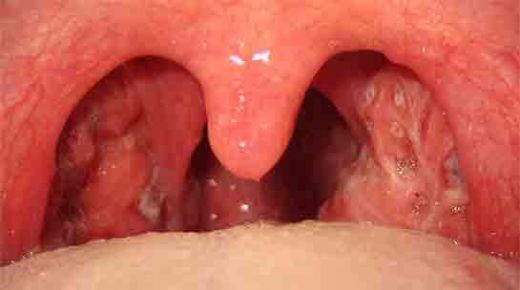

Sol bademcik şişmesi, genellikle boğazın arka kısmında yer alan lenfoid dokunun iltihaplanması veya enfekte olması durumudur. Bademcikler, bağışıklık sisteminin bir parçası olarak, vücut savunmasında önemli bir rol oynamaktadır. Bu durum, çeşitli etkenlerden kaynaklanabilir ve genellikle enfeksiyon belirtisi olarak ortaya çıkar.

Sol bademcik çürümeleri genellikle yutkunma zorluğu, boğazda tahriş, ağrı ve yüksek ateş gibi belirtilerle kendini gösterir. Bu durum, bademcik iltihabı veya diğer enfeksiyonların bir sonucu olabilir.

Alpartur, yaşadığın bu durum gerçekten de rahatsız edici olabilir. Boğazdaki ağrı ve yutkunma güçlüğü, günlük yaşamı olumsuz etkileyebilir. Beyaz lekelerin varlığı, enfeksiyon belirtilerine işaret edebilir ve bu nedenle doktora başvurman çok önemli bir adım.

Dikkat Edilmesi Gerekenler